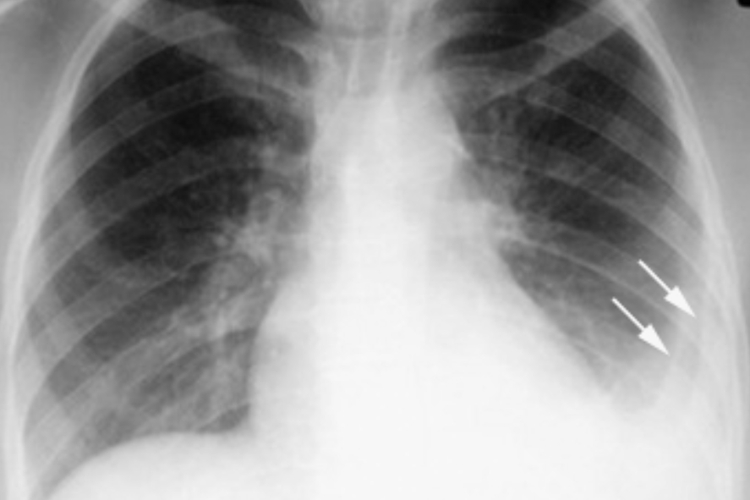

X线胸片呈哑铃形阴影,是典型的原发综合征,位于中上肺野,呈圆形、类圆形或局限性斑片影。若是肺门淋巴结结核可呈团块状、边界清晰和密度高的肿瘤型,或边界不清、伴有炎性浸润的炎症型。